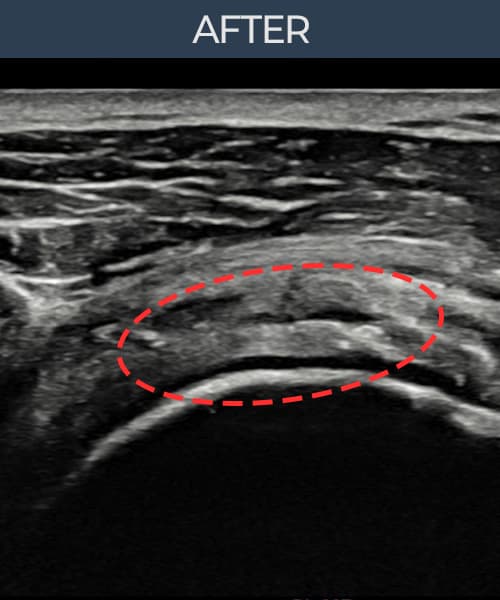

[経過期間: 23.07.18~23.09.14]

[縫縮術] 超音波検査にて左 棘上筋腱 광범위 部分断裂(15mm × 6mm (腱厚の約70%欠損))を確認。縫縮術施行後、腱の連続性が回復し、日常生活に復帰されました。